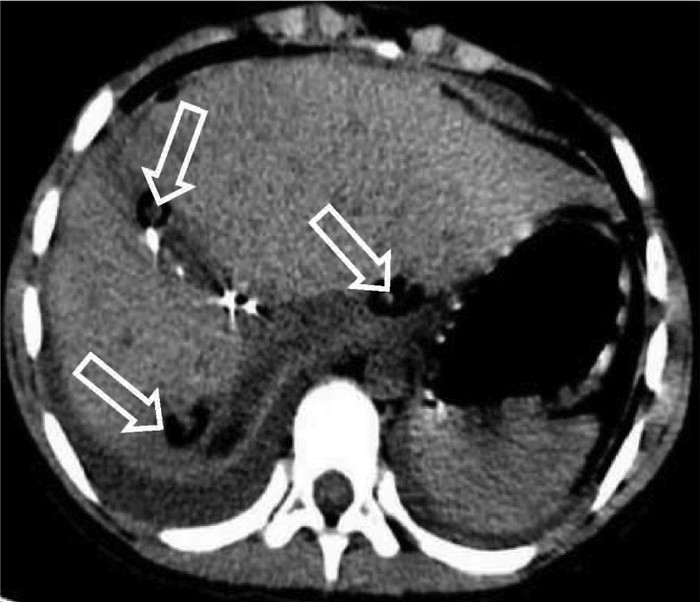

Hereditary hemorrhagic telangiectasia of the liver: A case report

Tingting WANG, Liang MA, Jianping CHEN

2022, 38(2): 423-425. DOI: 10.3969/j.issn.1001-5256.2022.02.032

Abstract(1009) HTML (348) PDF (2696KB)(39)

Abstract: